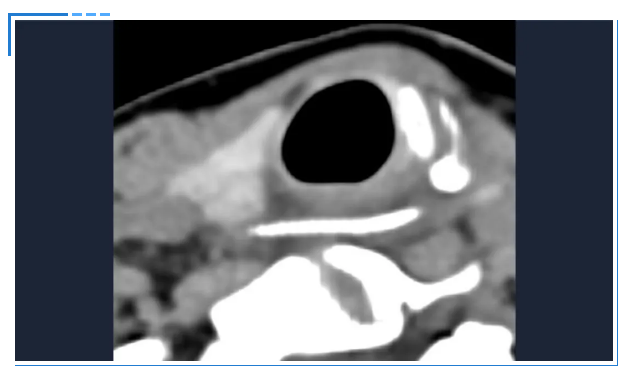

接诊的吕主任详细询问了陈女士的情况,结合她持续加重的咽痛,判断事情没那么简单。立即安排她进行双源CT检查并辅以三维重建技术。检查结果让所有人都捏了一把汗:一根近3公分长的鱼刺,深深卡在食管入口处,不仅位置刁钻,还已经刺穿食道,周围创面出现感染。

消化内镜室迅速启动取刺准备,当胃镜缓缓抵达食管入口时,清晰可见一根长约3cm的鱼刺,正斜斜嵌顿在食管入口的右侧壁,鱼刺尖端已刺入黏膜下层,周围黏膜因刺激出现明显充血水肿。更棘手的是,鱼刺恰好卡在食管入口的生理拐弯处,这个部位是食管与咽喉的衔接点,角度刁钻,内镜难以稳定固定位置。